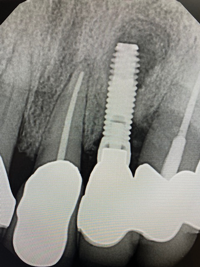

In this case, a dental implant that had been placed 10 years prior was functional, stable, and esthetically acceptable to the patient. However, a significant fistula was present on the facial-apical aspect of the ridge in the maxillary lateral incisor area. This area was painfully sensitive to touch and demonstrated purulence when squeezed. To evaluate the lesion, first, a conventional digital radiograph was acquired, which revealed an apical radiolucency at the apex of the implant (Figure 1). Further analysis using cone-beam computed tomography (CBCT) demonstrated a fistula from that site to the oral environment (Figure 2). Treatment options were discussed, including removal of the implant, followed by grafting, a healing period, and replacement of the implant and implant-retained crown. If this option was selected, a transitional appliance would need to be created. Another option was to attempt to salvage the implant and implant crown by treating the infection and grafting the site to create a new boney wall and eliminate the fistula. Ultimately, the patient accepted this option to attempt to salvage the fixture and crown.

(1.) Preoperative radiographic evaluation demonstrating a large radiolucency at the apical third of the body of an implant fixture replacing the patient’s maxillary left lateral incisor. The implant was stable, and the prosthesis was deemed esthetically acceptable by the patient.

Figure 1